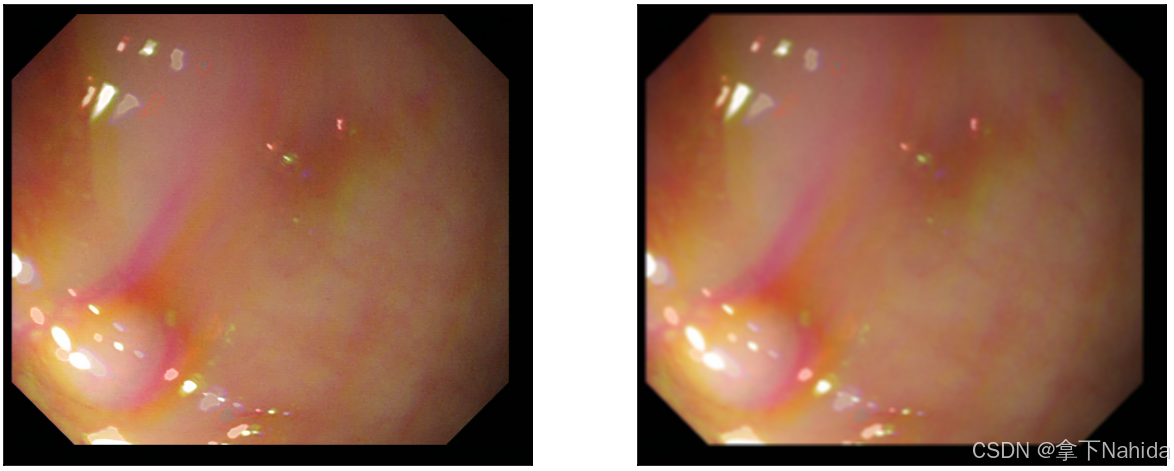

实例图如下。

看起来显得变得更模糊了,图像的颜色区间变化不那么尖锐,这样把噪点作出处理的同时牺牲了一定清晰度。